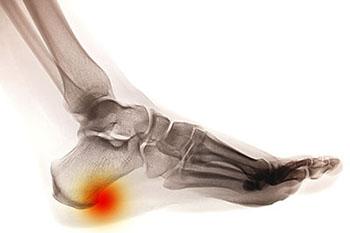

Heel Spurs

Heel spurs are brought upon by a calcium deposit that causes a bony protrusion on the underside of the heel bone. It normally forms over time and can best be diagnosed through an x-ray examination. Heel spurs are commonly linked with plantar fasciitis, an inflammation...